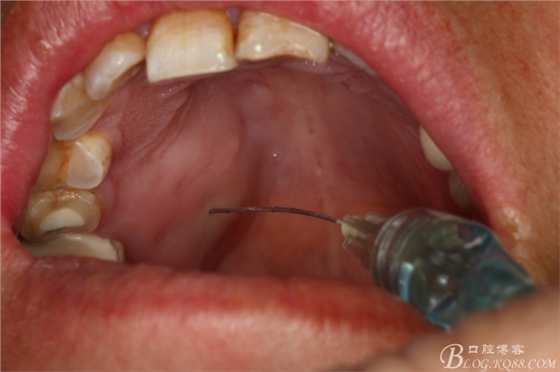

圖5.唇側(cè)局部浸潤麻醉